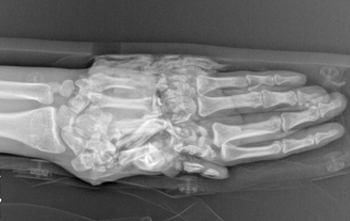

科室在肢體嚴重撕脫創(chuàng)傷、復雜斷指(肢)再植、各類型游離足趾移植拇手指再造或組合再造、游離皮瓣修復四肢缺損創(chuàng)面等方面取得顯著成績,受到了省內外專家和廣大患者高度評價。近年來,科室不斷拓寬診治范圍,深耕手病?,如腱鞘炎、周圍神經(jīng)損傷、肌腱修復等,在腕關節(jié)鏡微創(chuàng)治療方面取得了長足的進步,形成了自己的治療特色。

◎ 斷指(肢)再植 ◎ 游離足趾移植拇手指再造或組合再造

擅長:四肢顯微修復及功能重建;特殊類型斷指(肢)再植,小兒斷指再植;拇手指全型再造;小兒手足先天性畸形矯形、燒傷瘢痕整形;四肢骨缺損、手部各種腫瘤、周圍神經(jīng)損傷的診治;腱鞘炎、周圍神經(jīng)損傷、肌腱修復等;腕關節(jié)鏡的微創(chuàng)治療

擅長:嚴重四肢骨折,小兒骨折,老年人骨折的治療;肢體嚴重創(chuàng)傷顯微修復及功能重建;特殊類型斷指(肢)再植,拇手指再造;小兒先天性畸形矯形、燒傷瘢痕整形;四肢骨缺損、難治性創(chuàng)面修復;褥瘡、糖尿病足的治療;手部各種腫瘤、神經(jīng)損傷的修復

熟練掌握急嚴重創(chuàng)傷救治、對手(足)外科疾病的診治,包括斷指(肢)再植、拇手指再造、各種常見游離皮瓣和帶蒂皮瓣修復皮膚軟組織缺損、四肢骨折并血管神經(jīng)肌腱損傷、晚期手功能修復與重建、小兒多指畸形等。